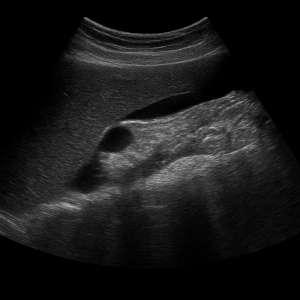

복부초음파는 우리 눈에 보이지 않는 높은 주파수의 소리(초음파)를 배 위에 대고 보내서, 몸속 장기와 혈관 구조를 실시간으로 영상으로 보는 검사입니다. 이 검사는 방사선을 사용하지 않고 통증이나 위험이 거의 없어, 안전하게 여러 번 반복할 수 있어요 .

초음파 기기에는 ‘탐촉자(transducer)’라는 작은 기계가 있는데, 이 기기가 전기 신호로 초음파를 만들어 몸속으로 보내요. 이때 사용하는 주파수는 사람이 들을 수 없는 높은 소리, 보통 2~5MHz 정도예요 .

초음파가 배 안 장기나 조직에 부딪히면 일부는 반사되어 돌아오고, 이 반사파를 탐촉자가 받아 전기 신호로 바꿔요. 컴퓨터가 이 신호를 이용해서 화면에 영상으로 보여줍니다 .

영상이 만들어지는 원리는 시간(반사파가 돌아오는 속도)과 강도(얼마나 세게 반사되었는지)를 컴퓨터가 계산해 이미지의 위치와 밝기를 결정하는 방식이에요. 깊이가 깊을수록 반사되는 시간도 길어지고, 반사파가 세면 화면에서 밝게 나타나요 .